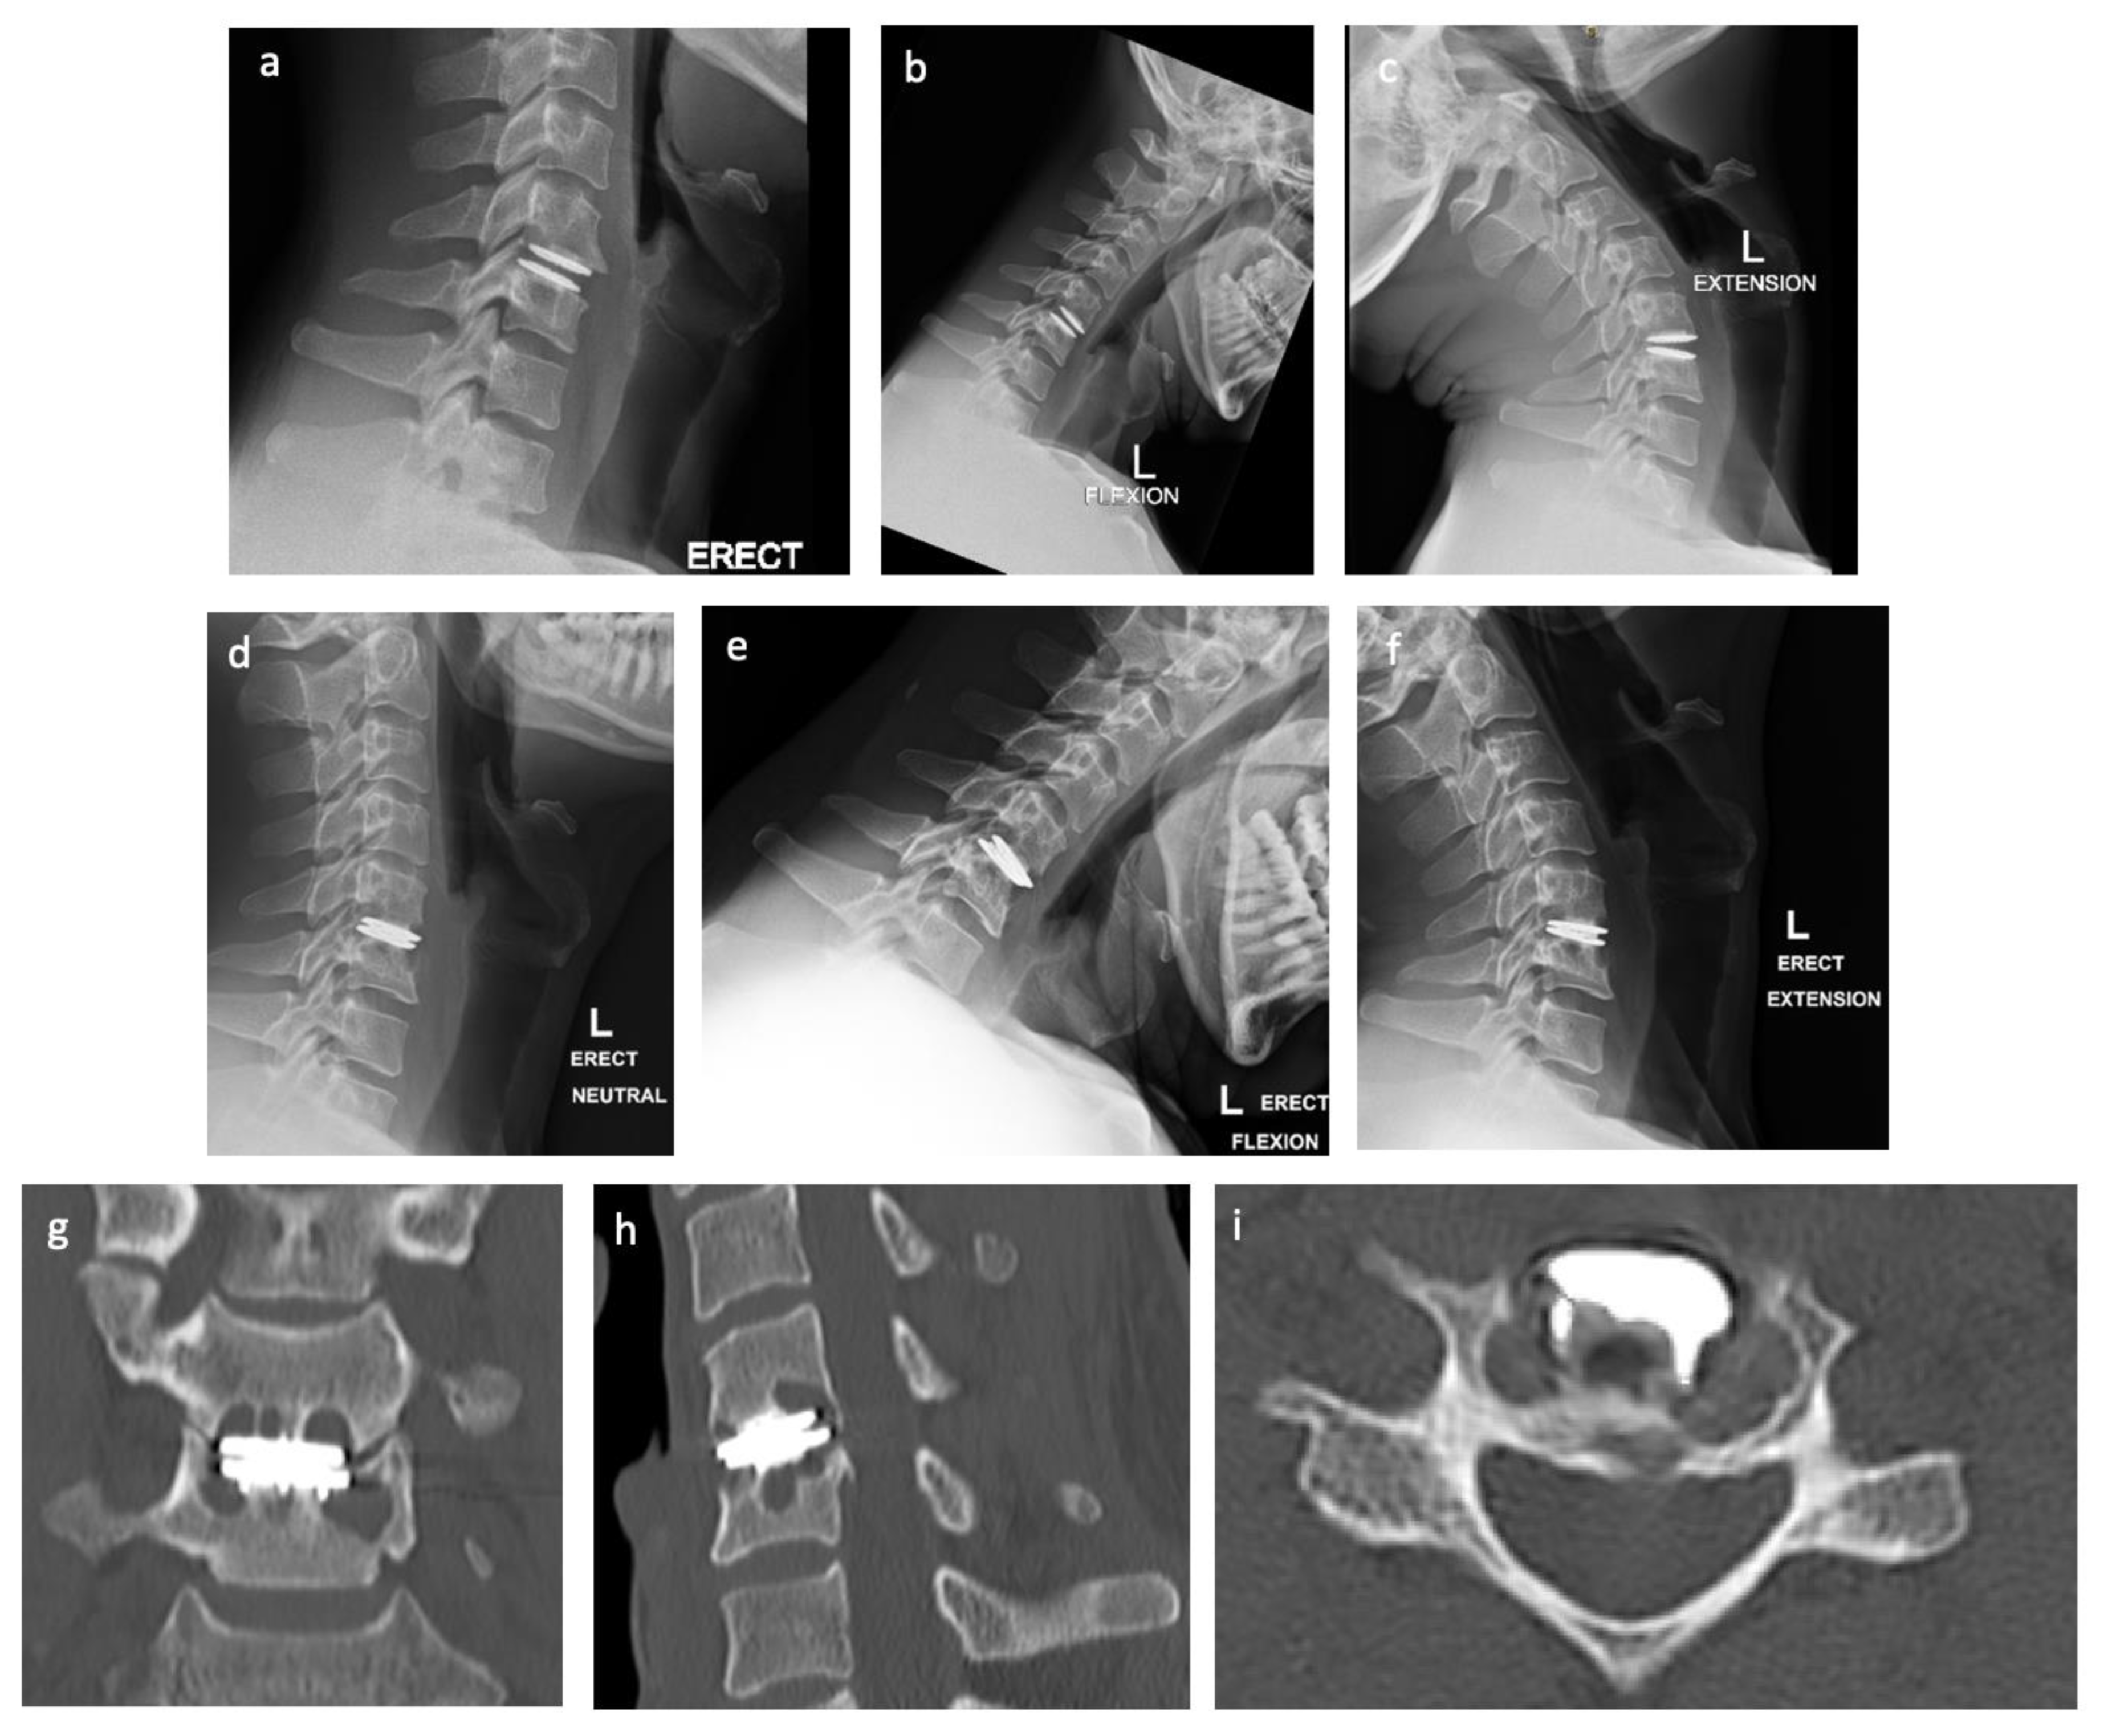

2.1. Case Presentation

2.2. Preoperative Planning